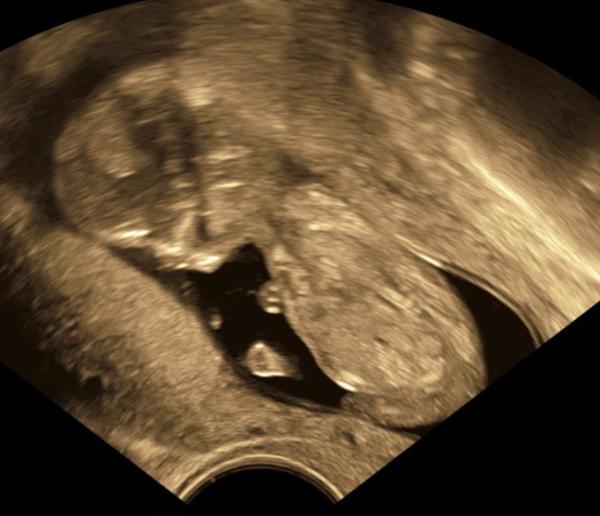

Bin heute bei 12+3 und Baby ist 6,71cm groĂ, alles gut sichtbar an Organen etc. und der PrĂ€natalmedizinier (Degum III) meint wir brauchen nicht verunsichert sein. Risiken fĂŒr die Trisomien sind sehr gering.

HĂ€nde und FĂŒĂchen konnten wir gut sehen auch. Und kurzzeitig saĂ unser Wunder richtig sĂŒĂ im Schneidersitz da

GMH muss bzw. sollte man maximal alle vier Wochen beobachten, aber sieht bisher alles gut aus. Von dem Myom konnte er nichts mehr sehen und die Durchblutung ist auch einwandfrei